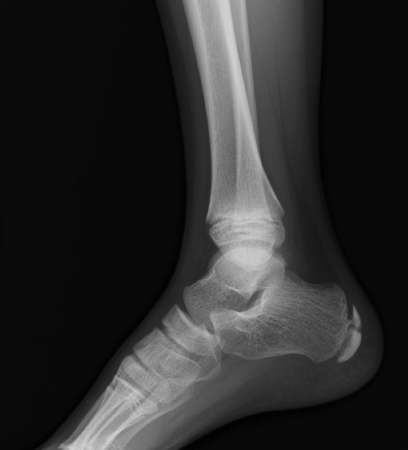

レントゲン写真ではこちらがわかりやすいかと思いますので引用させていただきます。